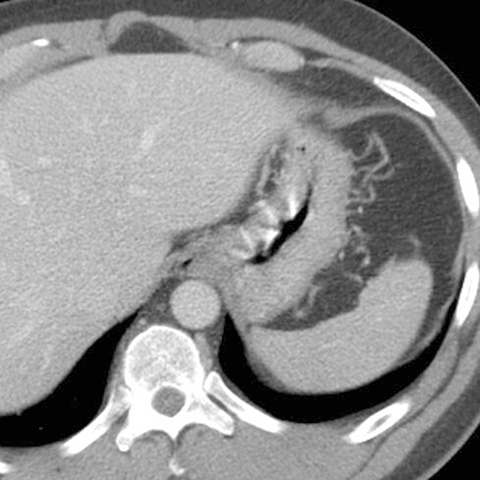

Normal spleen, axial view (CT) [1 of 5]